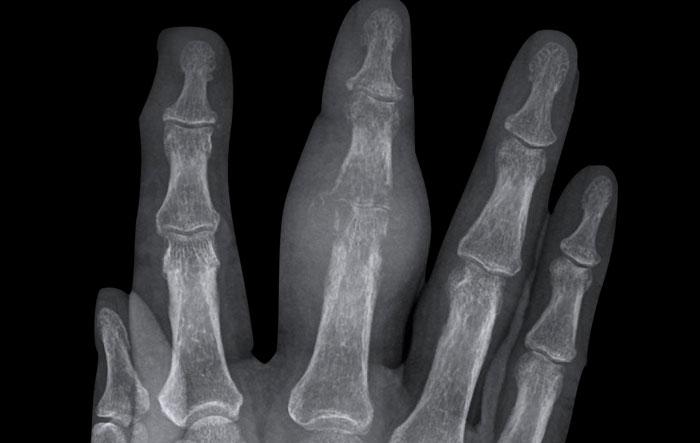

Hình ảnh điển hình của viêm ngón tay (dactylitis) “ngón xúc xích” với phù nề mô mềm và biến dạng bút chì trong cốc tại khớp liên đốt xa (DIP) 1-2 và 5 của bàn tay trái ở bệnh nhân viêm khớp vảy nến.

Lưu ý rằng các khớp bàn ngón tay (MCP) không bị tổn thương (khác với viêm khớp dạng thấp).